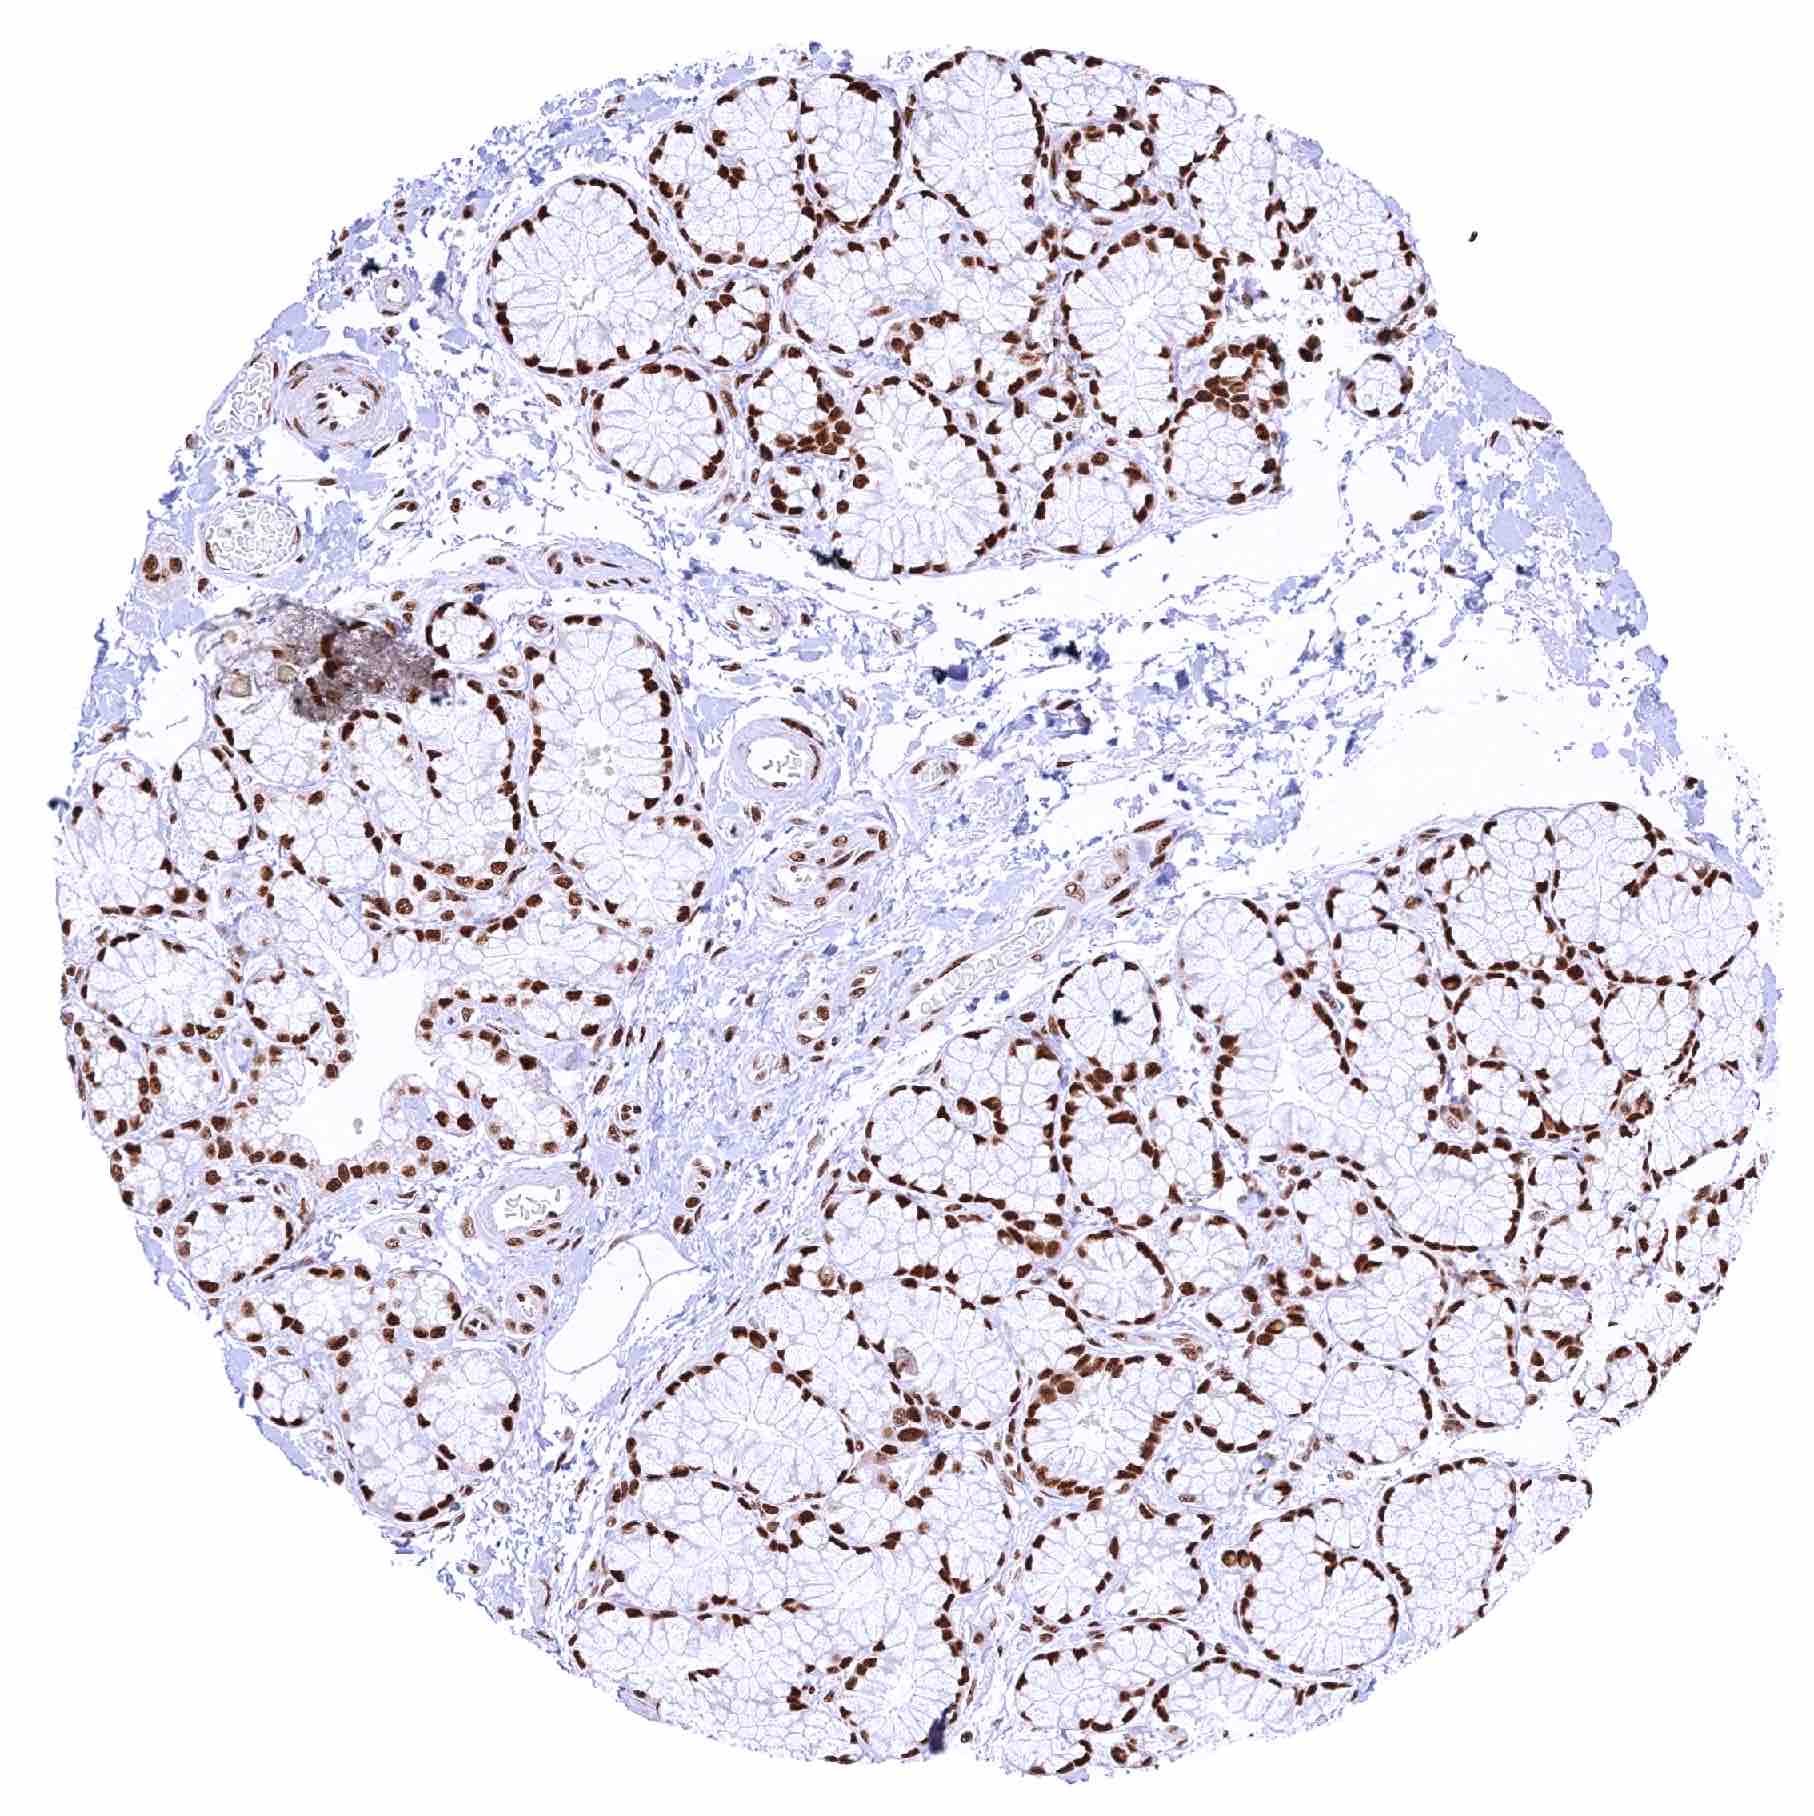

Testis – Distinct nuclear MRE11 staining of all cells although the staining intensity of germ cells decreases from spermatogonia to spermatids